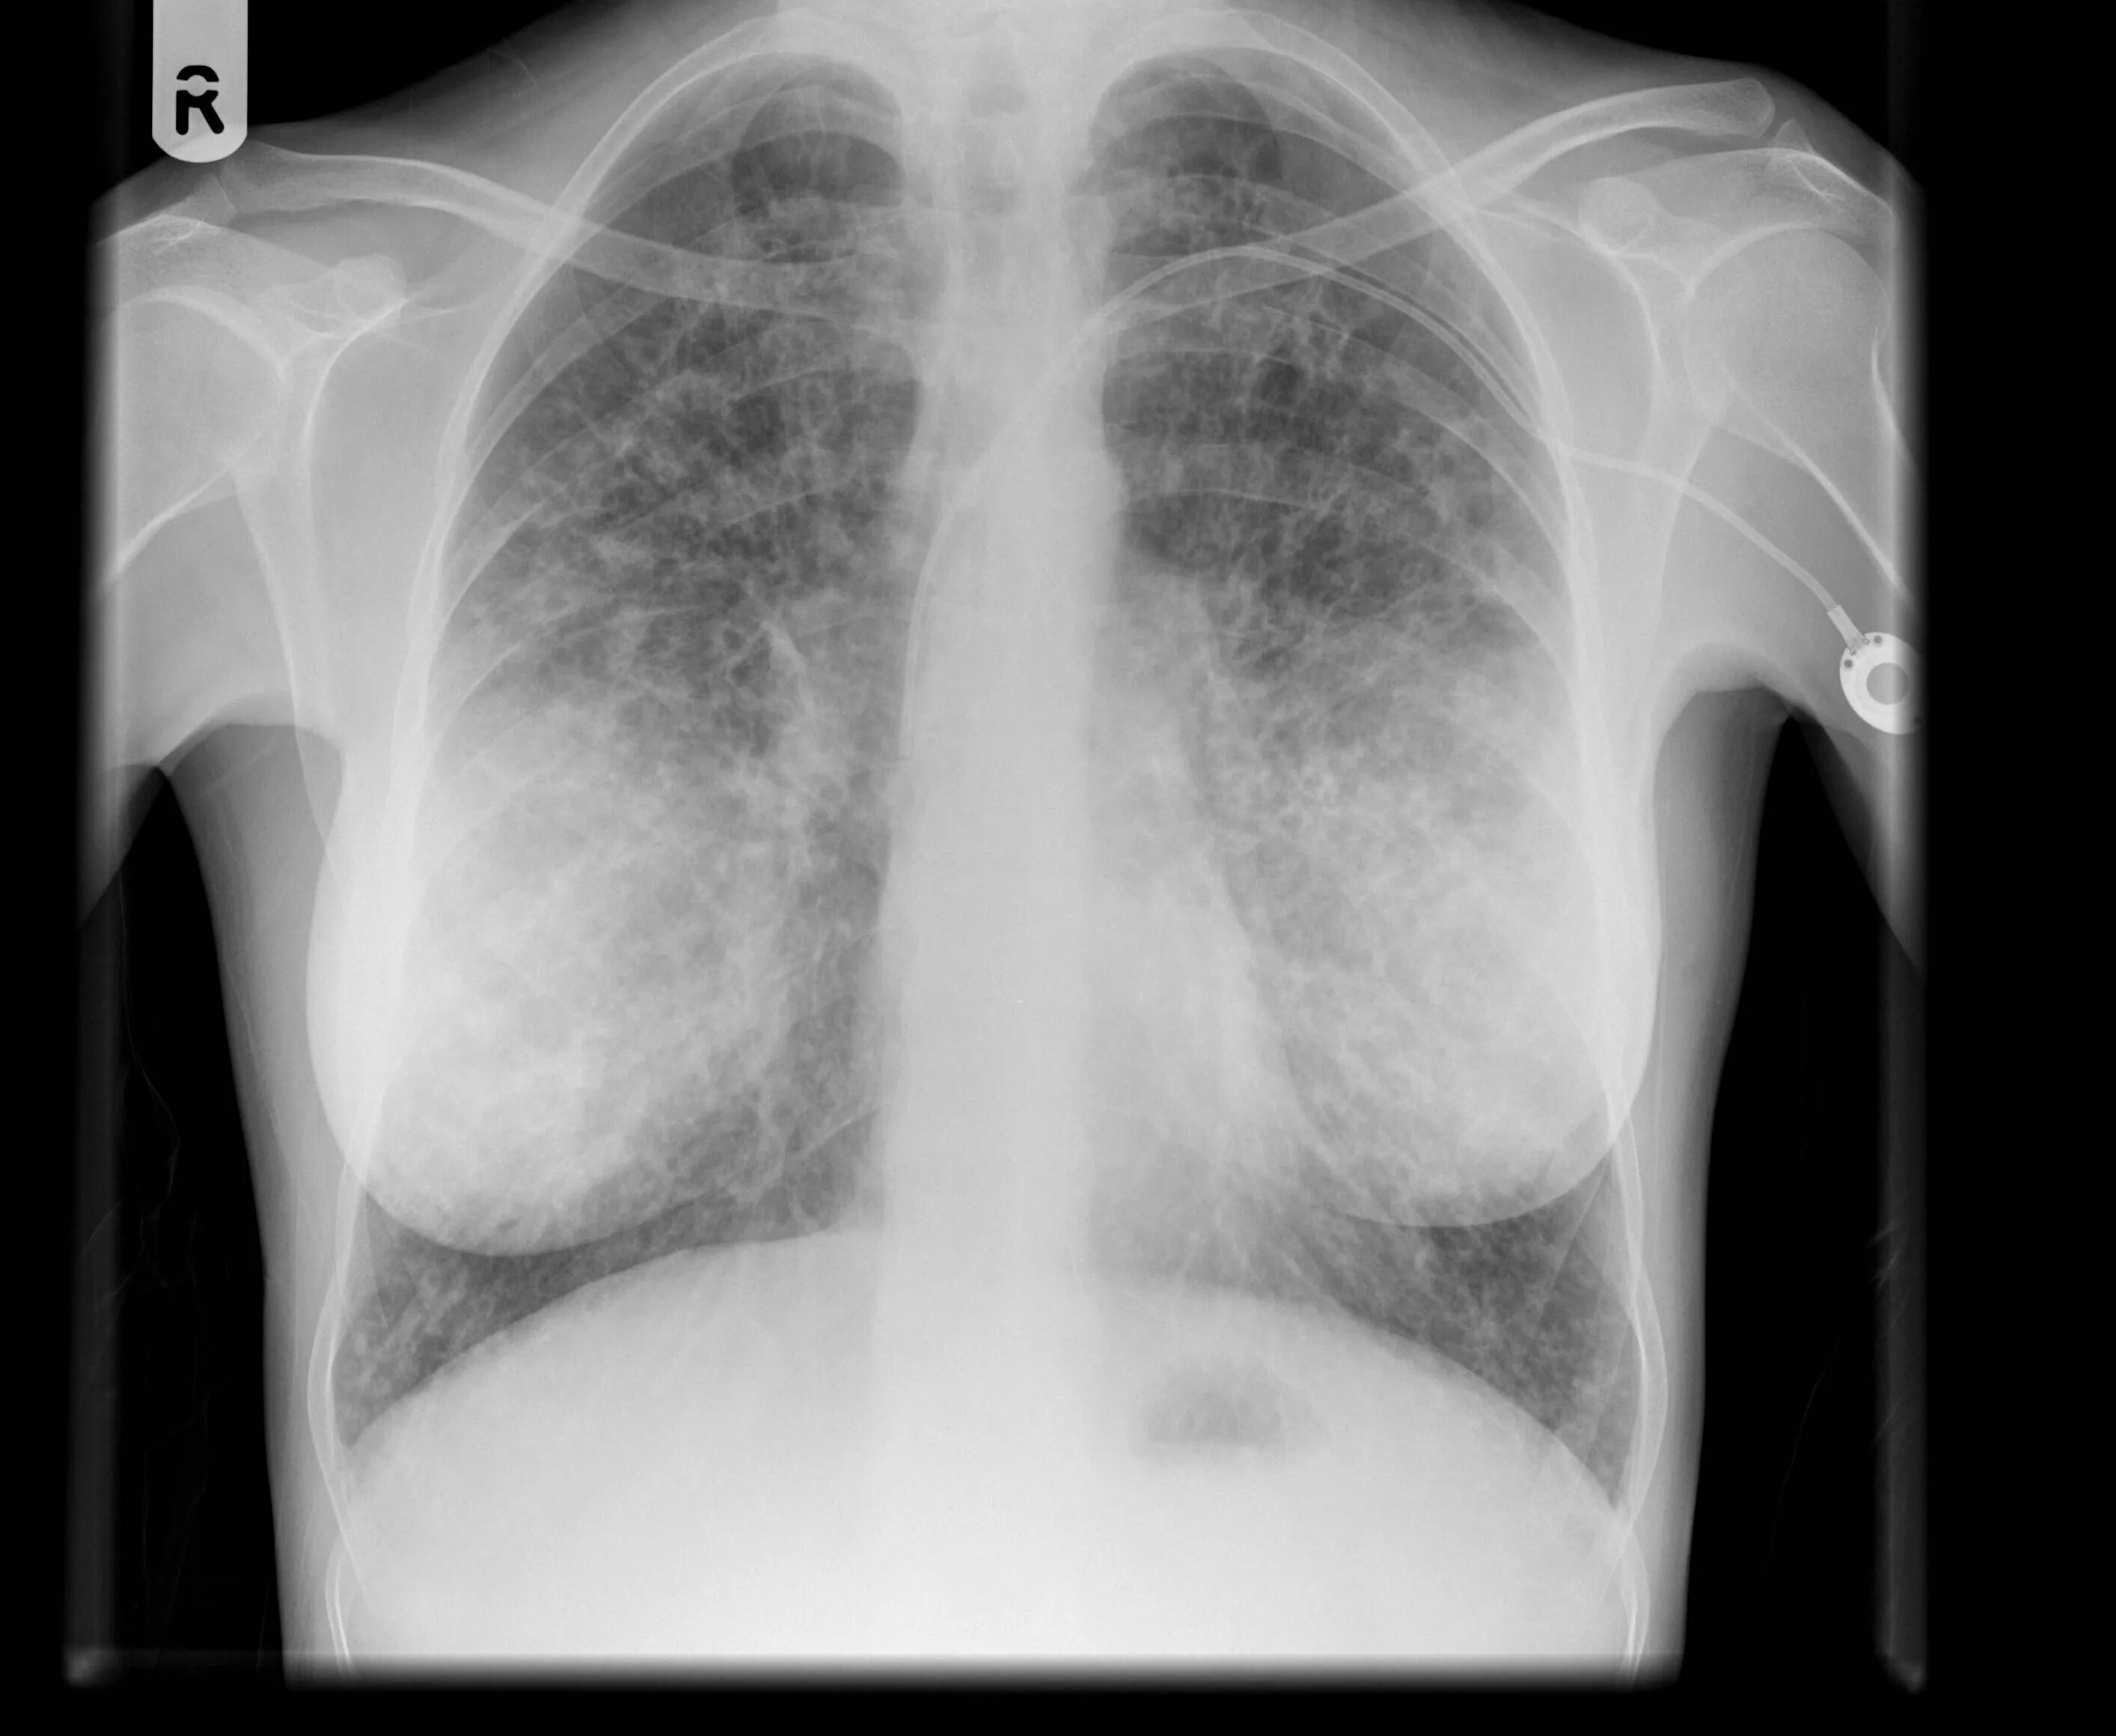

Как выглядит фиброз легких